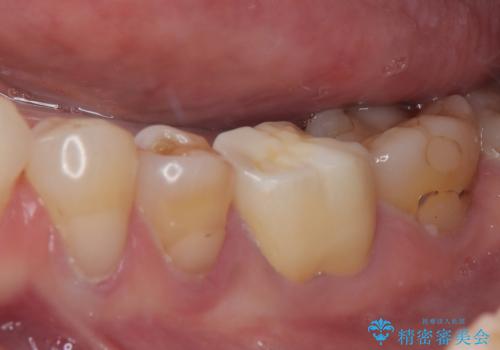

- 奥歯がたまにしみることがあるとのことで来院された患者様です。

特に問題となるような歯髄症状はなく、装着されている詰め物の境目がしみているような状態でした。

相談の上、フルジルコニアクラウンにて補綴治療を行うこととしました。